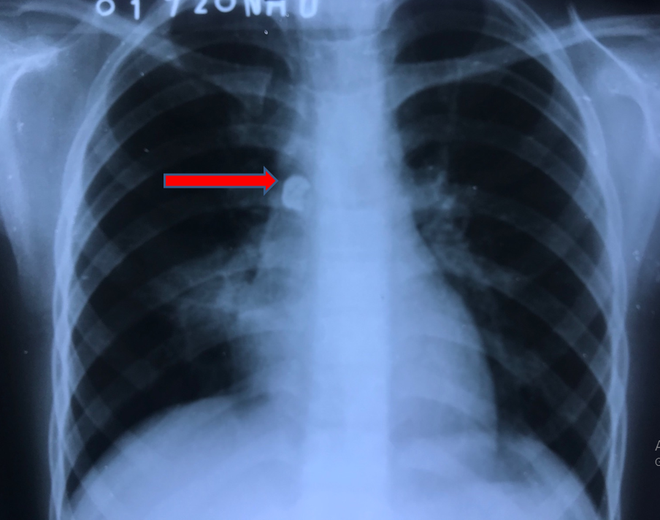

Tự nhổ răng tại nhà, bé gái bị viêm phổi nặng nguy hiểm tính mạng ảnh 1Hình ảnh X-quang cho thấy dị vật nằm trong phổi. Ảnh minh họa. (Nguồn: bvndtp.org.vn)

Đến Bệnh viện Đa khoa tỉnh Đồng Tháp, sau khi chụp CT, các bác sỹ phát hiện một dị vật cản quang có hình chiếc răng trong phổi.

Xác định có dị vật là chiếc răng ở trong phổi, bệnh nhi được chuyển lên Bệnh viện Nhi đồng Thành phố. Tại đây, thông qua các biện pháp chẩn đoán hình ảnh, các bác sĩ nhận thấy một chiếc răng hàm cắm sâu vào thành phế quản, gần như bít hoàn toàn phế quản gốc phải của bệnh nhi.